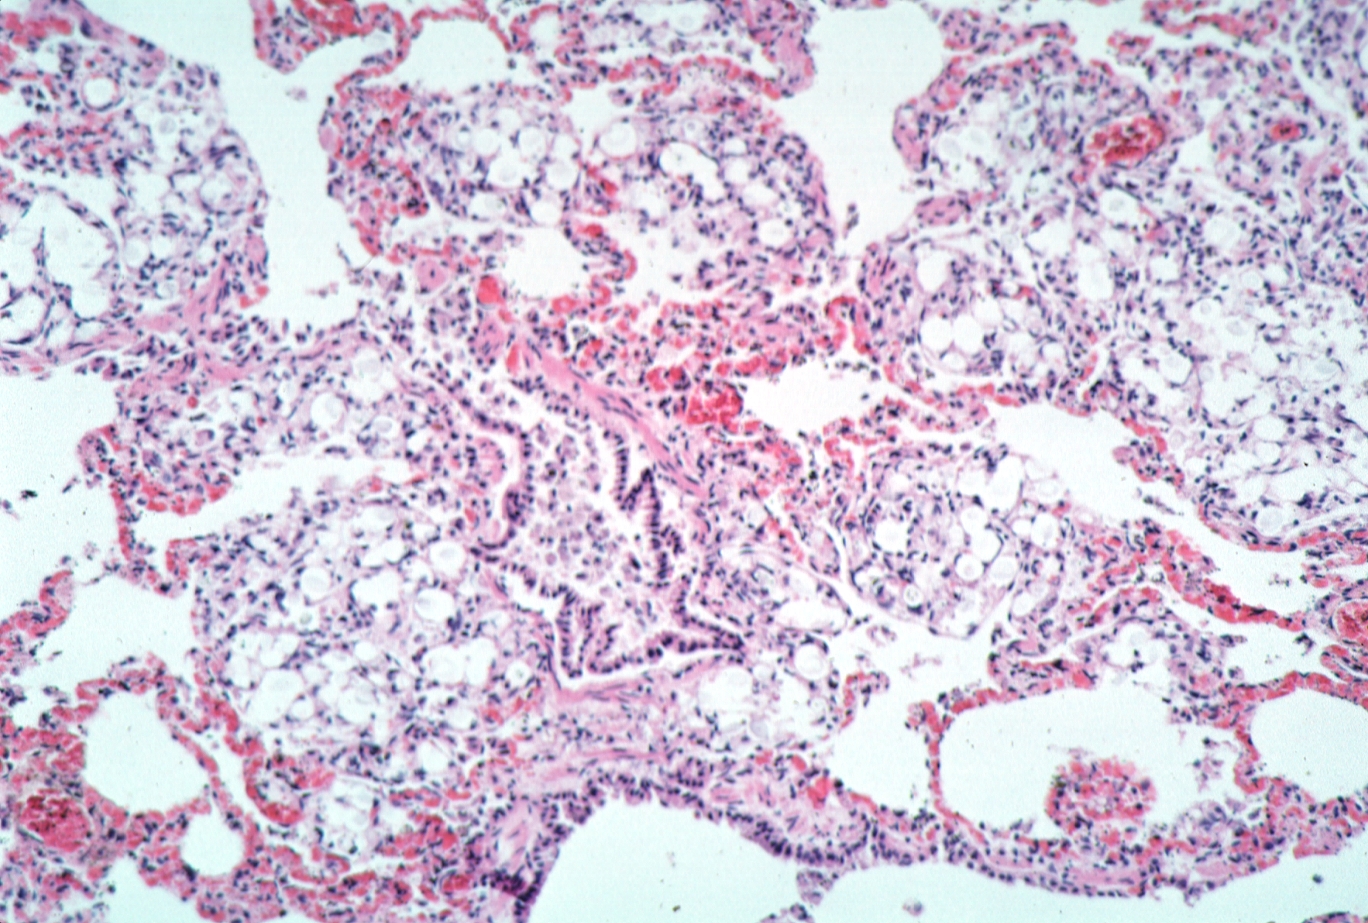

HISTOLOGY: RESPIRATORY: Lung, cryptococcosis